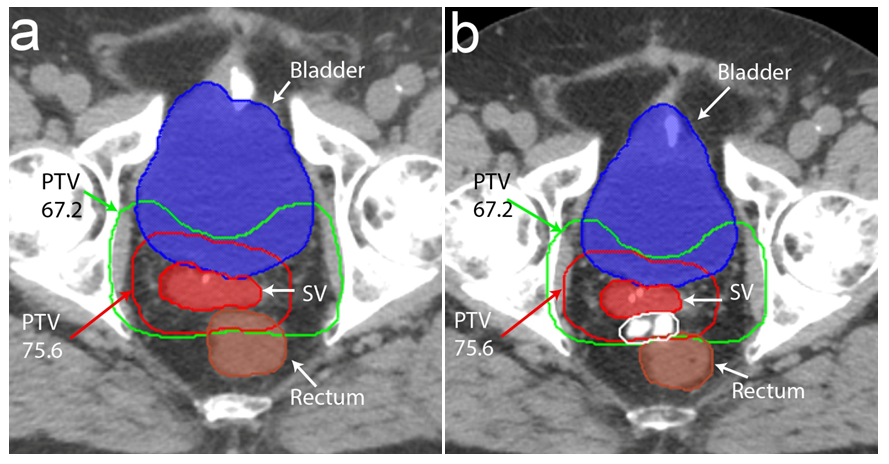

The bladder was contoured from apex to base. The rectum was contoured as a whole solid structure beginning at 1.0cm above the most superior level of the PTV to the anorectal junction as per departmental protocol. In order to determine the effect of the HS for each patient, two treatment plans were created from the baseline pre-HS CT and the post-HS CT+/-MRI scans (Figure 2). Pre-HS treatment plans were created from either CT simulation scans performed prior to the HS insertion or reconstructed from diagnostic CT scans performed during the patient’s initial workup. The degree of separation achieved between the anterior rectal wall and the posterior edge of prostate bed was quantified for the pre-HS and post-HS treatment plans. The rV30, rV40, rV50, rV60, rV70, rV75 and rV78 were compared. The low dose (67.2Gy) and high dose (75.6Gy) PTV volumes, rectal volume and D95 for PTV67.2 and PTV75.6 were also compared to ensure consistency between the pre-HS and post-HS treatment plans.

Figure 2 Pre-hydrogel spacer (HS) and post-HS treatment planning scans showing bladder (solid blue), rectum (solid brown), seminal vesicle recurrence (solid red), low dose PTV (PTV67.2) in green and high dose PTV (PTV75.6) in red. The iodinated HS is hyperintense on computer tomography (delineated by white line) and displaces the rectum posteriorly. The low and high dose PTV transects the rectum in the pre-HS treatment planning scan but is situated on the anterior surface of the rectum post-HS.